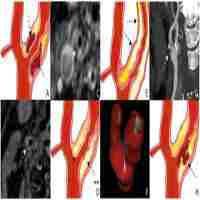

| Description | Atheromatous disease is the first cause of death and dependency in developed countries and carotid artery atherosclerosis is one of the main causes of severe ischaemic strokes. Current management strategies are mainly based on the degree of stenosis and patient selection has limited accuracy. This information could be complemented by the identification of biomarkers of plaque vulnerability, which would permit patients at greater and lesser risk of stroke to be distinguished, thus enabling a better selection of patients for surgical or intensive medical treatment. Although several circulating protein-based biomarkers with significance for both the diagnosis of carotid artery disease and its prognosis have been identified, at present, none have been clinically implemented. This review focuses especially on the most relevant clinical parameters to take into account in routine clinical practice and summarises the most up-to-date data on epigenetic biomarkers of carotid atherosclerosis and plaque vulnerability. |